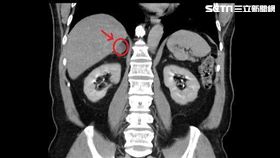

解尿困難拖到尿不出來 膀胱驚成蜂窩

攝護腺肥大症一直是困擾老年男性的主要問題之一,攝護腺...

吃藥血壓仍控制不佳 恐是腎上腺腫瘤

常常有許多病人門診中抱怨高血壓控制一直不如預期,儘管...